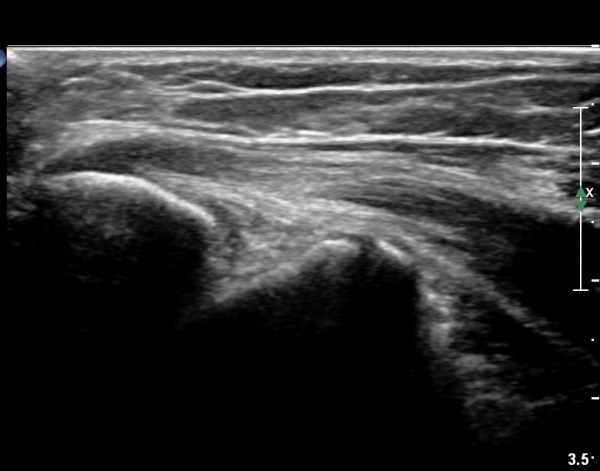

ÃÊÀ½ÆÄ °Ë»ç

³»»ó°ú Á¾´Ü¸é°Ë»ç¿¡¼­ ³»»ó°ú ±¼°ñ°Ç ºÎÂøºÎ¿¡ Àú¿¡ÄÚ º´º¯ÀÌ °üÂûµÈ´Ù. °Ç ½ÉºÎÀÇ

³»ÃøºÎÀδë´Â ƯÀÌ ¼Ò°ßÀ» º¸ÀÌÁö ¾Ê´Â´Ù(±×¸² 1, 2).